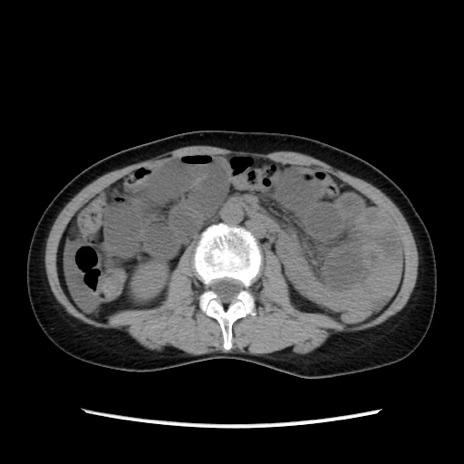

症例32(横断像)

【症例】40歳代 女性

【主訴】上腹部痛、嘔気・嘔吐

【現病歴】約9時間前頃から急に上腹部痛、嘔気、嘔吐が出現。改善しないため救急要請。

【既往歴】子宮頚癌(広汎子宮全摘術、放射線療法)、腸閉塞

【身体所見】腹部:平坦、軟、腸雑音亢進、上腹部を中心に腹部全体に圧痛あり。

【データ】WBC 8400、CRP 0.03